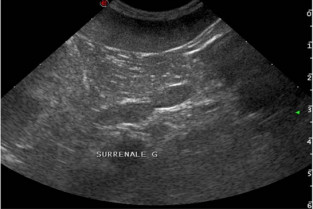

- reconnaître et d’identifier les lésions échographiques spléniques, ganglionnaires et

surrénaliennes - inclure les conclusions échographiques dans une démarche diagnostique plus large